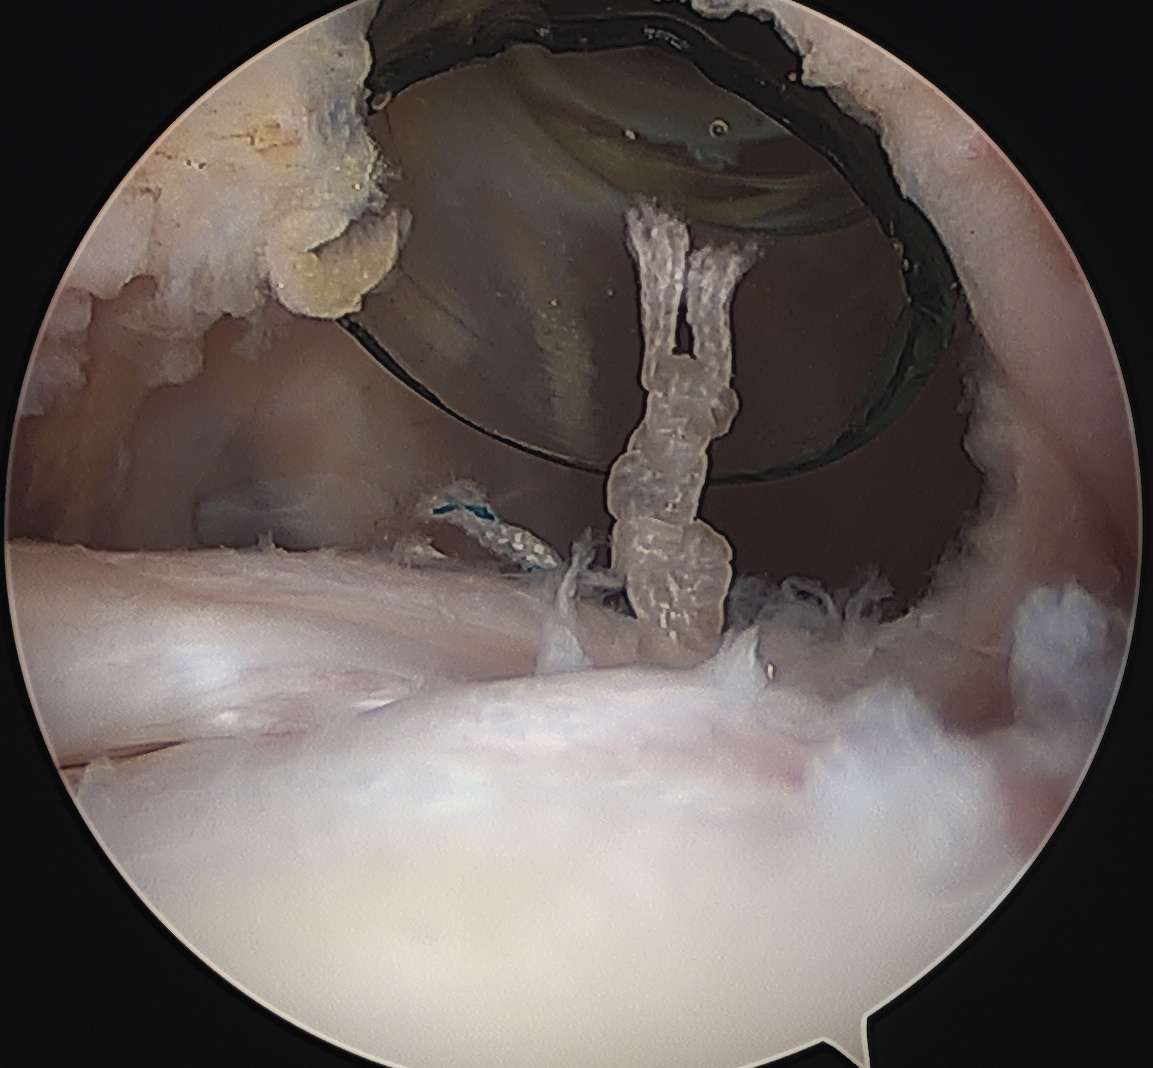

Lateral traction sutures placed in subscapularis, then cautery used to remove scar tissue and recreate rotator interval